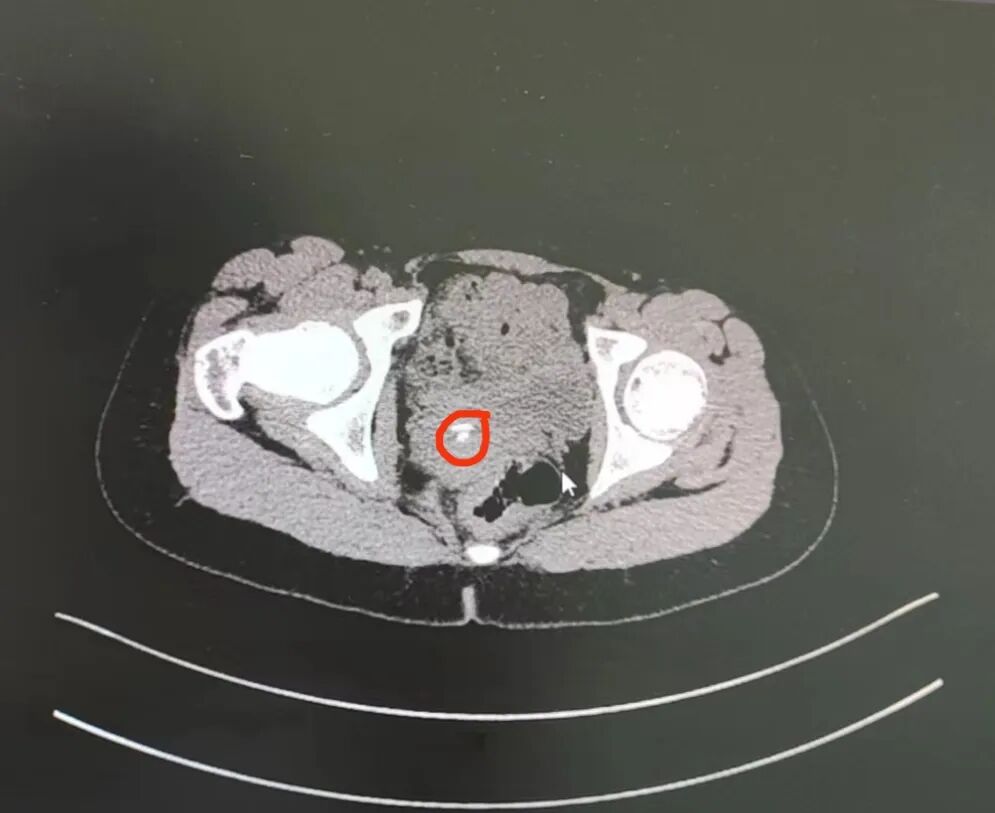

在给患儿完善了核酸检测及磁共振MRI检查后,医生发现报告结果提示阴道上段有两枚类圆形异物影。

在进一步肛查后,检查结果也显示可扪及阴道上段有两枚圆形的异物。

引发腹痛的原因有很多,比如囊肿等,鉴于孩子腹痛已经挺长时间了,医生建议家长先带孩子做影像学检查,检查结果提示有尖锐的物品在阴道穹隆-宫颈区里,正是这个“尖东西”引起的腹痛,医生当即意识到有异物,给孩子做了手术。